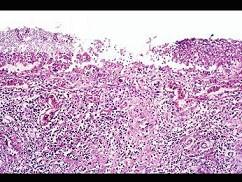

问题 根据图,关于菌痢的病理改变正确的是 ( )

选项 A.黏膜充血、水肿、中性粒细胞和巨噬细胞浸润 B.粘膜下层、肌层、浆膜层有明显的炎症反应 C.假膜主要为纤维素、坏死的肠粘膜、细菌、嗜中性粒细胞及红细胞等,部分有脱落 D.整个肠粘膜有假膜覆盖,粘膜上皮及腺体大片消失 E.大约一周左右,假膜开始脱落,形成大小不等,形状不一的“地图状”溃疡如图

答案 ABCDE